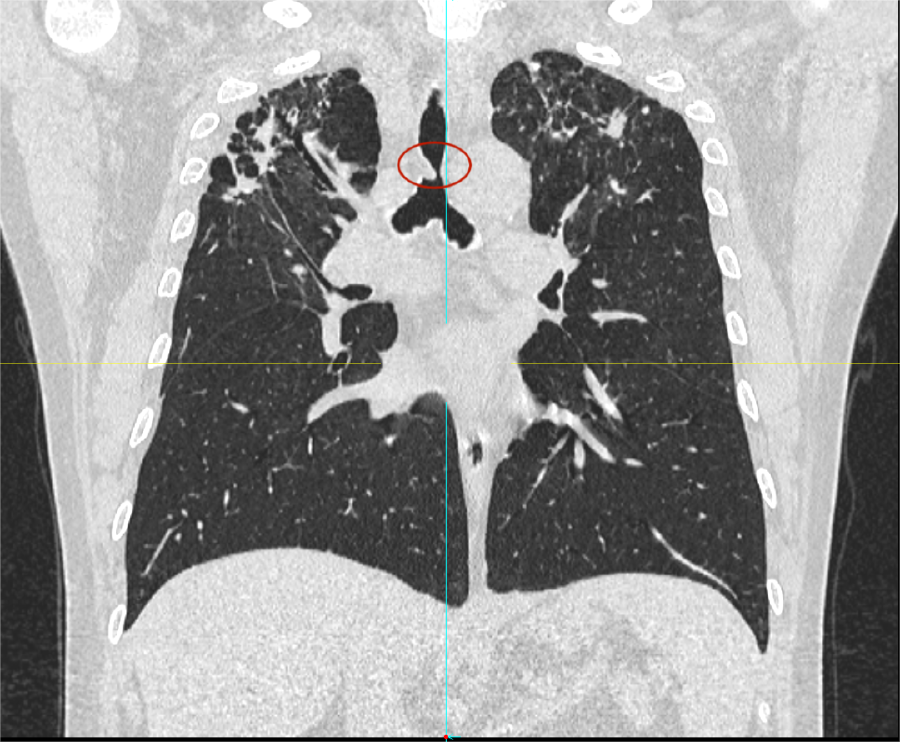

日前,患者趙先生(化名)因進行性呼吸困難來到河南省胸科醫(yī)院尋求治療,經(jīng)檢查確診為支氣管結(jié)核導致氣管中下段重度瘢痕性狹窄,最窄處直徑僅約3mm,且局部軟骨環(huán)破壞、塌陷,這意味著支撐氣道的結(jié)構(gòu)遭到損毀,通氣功能嚴重受損,且因狹窄部位靠近隆突,治療操作風險極高,稍有不慎就可能導致大出血、氣道完全閉塞等致命并發(fā)癥。

面對這一復雜情況,呼吸內(nèi)鏡中心主任王振靜組織結(jié)核內(nèi)科、麻醉科、醫(yī)學影像科等多學科會診。經(jīng)全面評估,團隊制定了詳細的手術(shù)方案:在全麻下,先行球囊擴張狹窄段,再經(jīng)硬質(zhì)支氣管鏡置入個體化制作的Y型硅酮支架,以支撐氣道結(jié)構(gòu)、恢復通暢。

在硬質(zhì)支氣管鏡引導下,手術(shù)團隊首先對狹窄部位進行球囊擴張。隨后,將術(shù)前根據(jù)患者三維CT數(shù)據(jù)定制的Y型硅酮支架精準覆蓋于氣管狹窄段。該支架確保與患者自身的氣道解剖結(jié)構(gòu)完美貼合,實現(xiàn)最佳支撐效果,并最大限度減少粘膜刺激增生等特點。支架展開后穩(wěn)定支撐于隆突及雙側(cè)主支氣管,氣道狹窄立即得到解除。